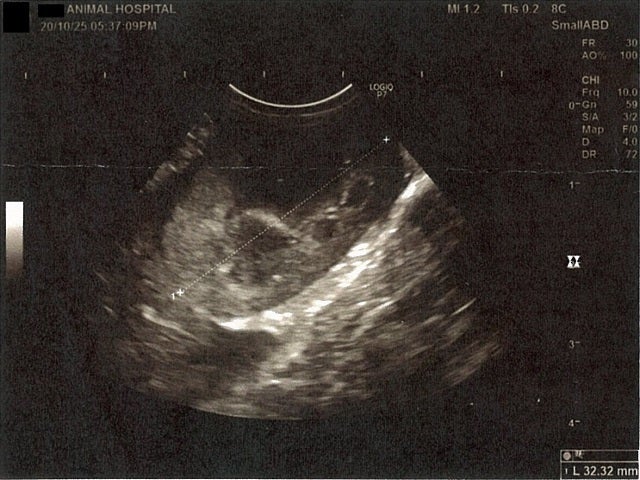

膀胱周りに腹水が確認できるエコー写真

《心臓周りの胸部以外の全ての腹部で腹水がみられるとの診断です》

大網という部分で内臓を包む膜のようなものです。その周りに腹水が溜まっています。